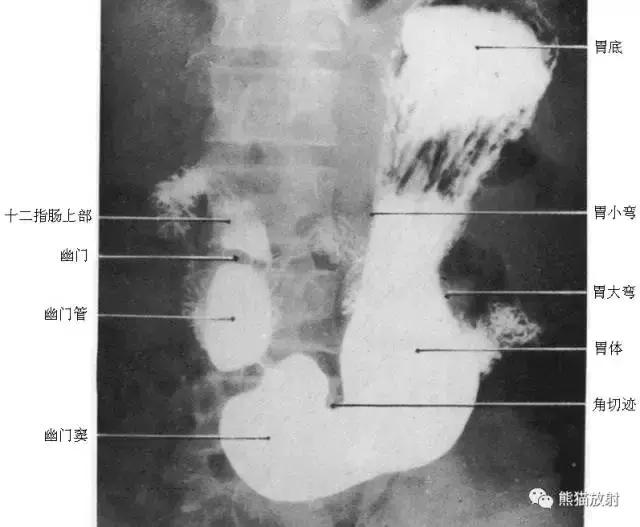

图24 胃X线像